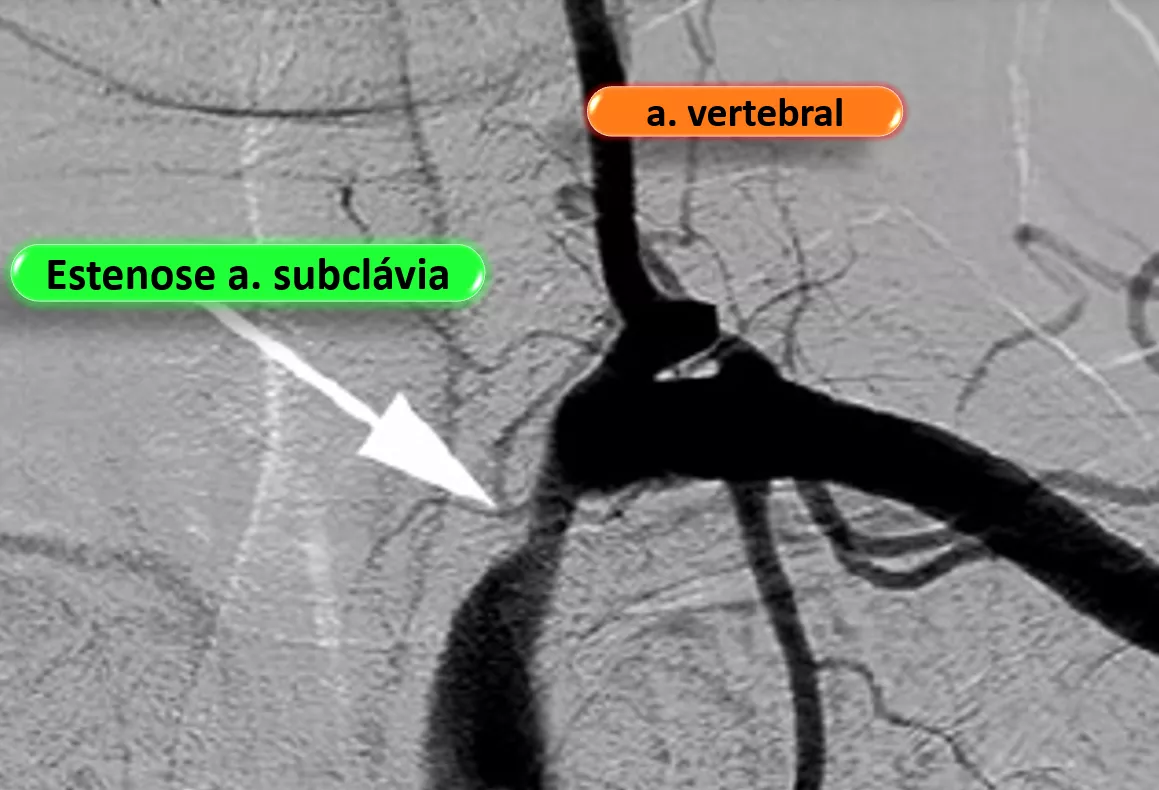

Neste curso imperdível, vamos abordar as alterações de fluxo da vertebral por roubo da subclávia. Aprenda a interpretar a análise espectral antes e depois do roubo, seja ele parcial ou total da artéria subclávia.

• Definição de roubo da artéria subclávia

• Diferença entre síndrome e fenômeno do roubo da subclávia

• Diagnóstico do roubo da subclávia

• Quais são os critérios atuais diagnósticos ultrassonográficos da estenose da subclávia